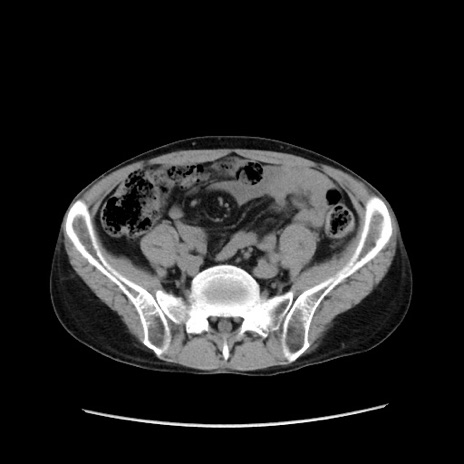

症例37(横断像)

【症例】40歳代 男性

【主訴】腹痛

【現病歴】4時間ほど前に電車に乗車中に臍部上より腹痛出現。徐々に増悪し起立困難となり、救急外来受診。生ものは数日食べていない。今朝お雑煮を食べた。

【身体所見】BT 36.8℃、BP 117/84mmHg、HR 91/min、SpO2 97%、苦悶様、腹部:臍上部広範囲圧痛あり、反跳痛±

【データ】WBC 8100、CRP 0.03